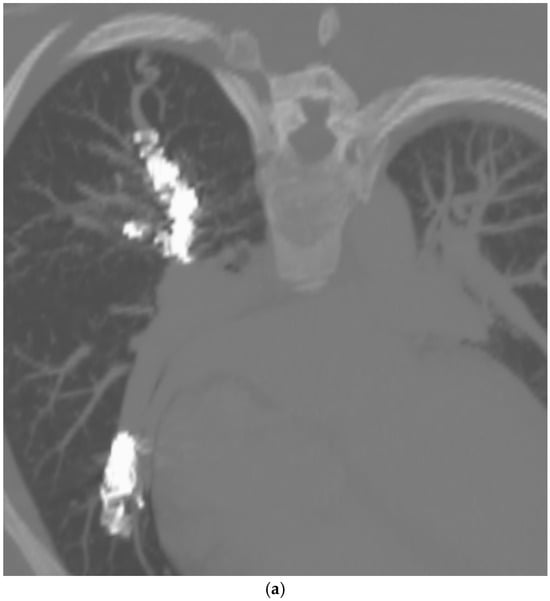

Figure 2.

A 32-year-old female with HHT with previous PAVM embolization, presents with worsening extertional dyspnea. (a) CT of the chest, oblique anteroposterior view with maximal intensity projection (MIP), demonstrating loosely packed coils resulting in a recanalized RUL PAVM. (b) Angiogram of the RUL PAVM confirms recanalization. This was subsequently successfully embolized with a microvascular plug MVP-7Q and two additional coils.

These criteria were confirmed angiographically, with criteria 1 demonstrated angiographically as recanalization (Figure 2a,b). Criteria 2, combines accessory feeding arteries and pulmonary collaterals together as they are generally difficult to differentiate angiographically (Figure 3a,b). Criteria 3 is angiographically shown as perfusion of the PAVM outflow via injection of systemic arteries (Figure 4a,b).

The proposed reintervention criteria were based off the greater than 30 years of experiences at a single large HHT center of excellence. The reintervention criteria described in this paper may be used as general guidelines but may not always be generalized to each patient and practice. Additionally, as the population in this study only included adults, it may not be applicable to the pediatric population. The first indication of reintervention requires experience evaluating the embolic devices. A contrast-enhanced chest CT must be windowed in such a way to see the degree to which contrast flows through the embolic device(s). If a column of contrast is measured to be approximately greater than 2–3 mm through, this would suggest a need for reintervention (Figure 2a,b). This may be difficult to determine, and evaluation of the scout images can be helpful to see how well the coil is packed. The second indication for reintervention involves the treatment of accessory pulmonary collaterals (Figure 3a–e). Accessory pulmonary collaterals are a result of adjacent pulmonary vessels which fill the feeding artery or sac beyond the embolic device(s). When this collateral vessel is greater than 2–3 mm, reintervention is indicated. The third criteria involve the treatment of systemic collaterals (Figure 4a–c). This is by far the most complicated issue to address and was the cause of the sole case of iatrogenic stroke. Luckily these systemic collaterals are rare, with a lifetime prevalence of 1.0% [13]. The author’s institutions experience treating these systemic collaterals was previously published. Patients with previously treated PAVMs presenting with hemoptysis are often due to systemic collaterals. In some cases, these lesions can be clearly identified on a chest CTA; however, this is not always the case and therefore a clinical presentation of hemoptysis is enough to indicate reintervention and interrogation of the systemic arteries. Understanding the best way to treat these lesions is an ongoing process.